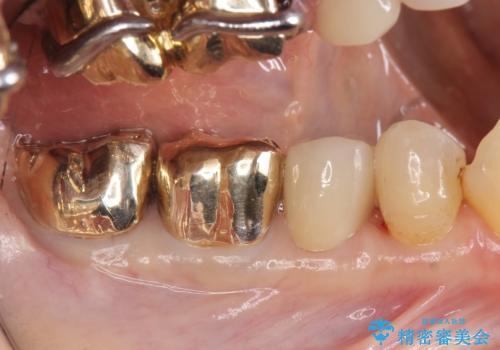

- 右下の古い銀歯のやり替えを希望された方の症例です。

口腔外から見えやすい 4 番目、5 番目の歯はセラミックによる審美的な治療を行い、6 番目、 7 番目の奥歯 2 歯は適合性に優れたPGA(ゴールド)クラウンによる治療を行いました。

- PGAクラウン…¥80,000×2、オールセラミッククラウン…¥100,000、仮歯…¥10,000×3、ファイバーコア…¥20,000、セラミックインレー…¥70,000費用は治療当時の料金となります